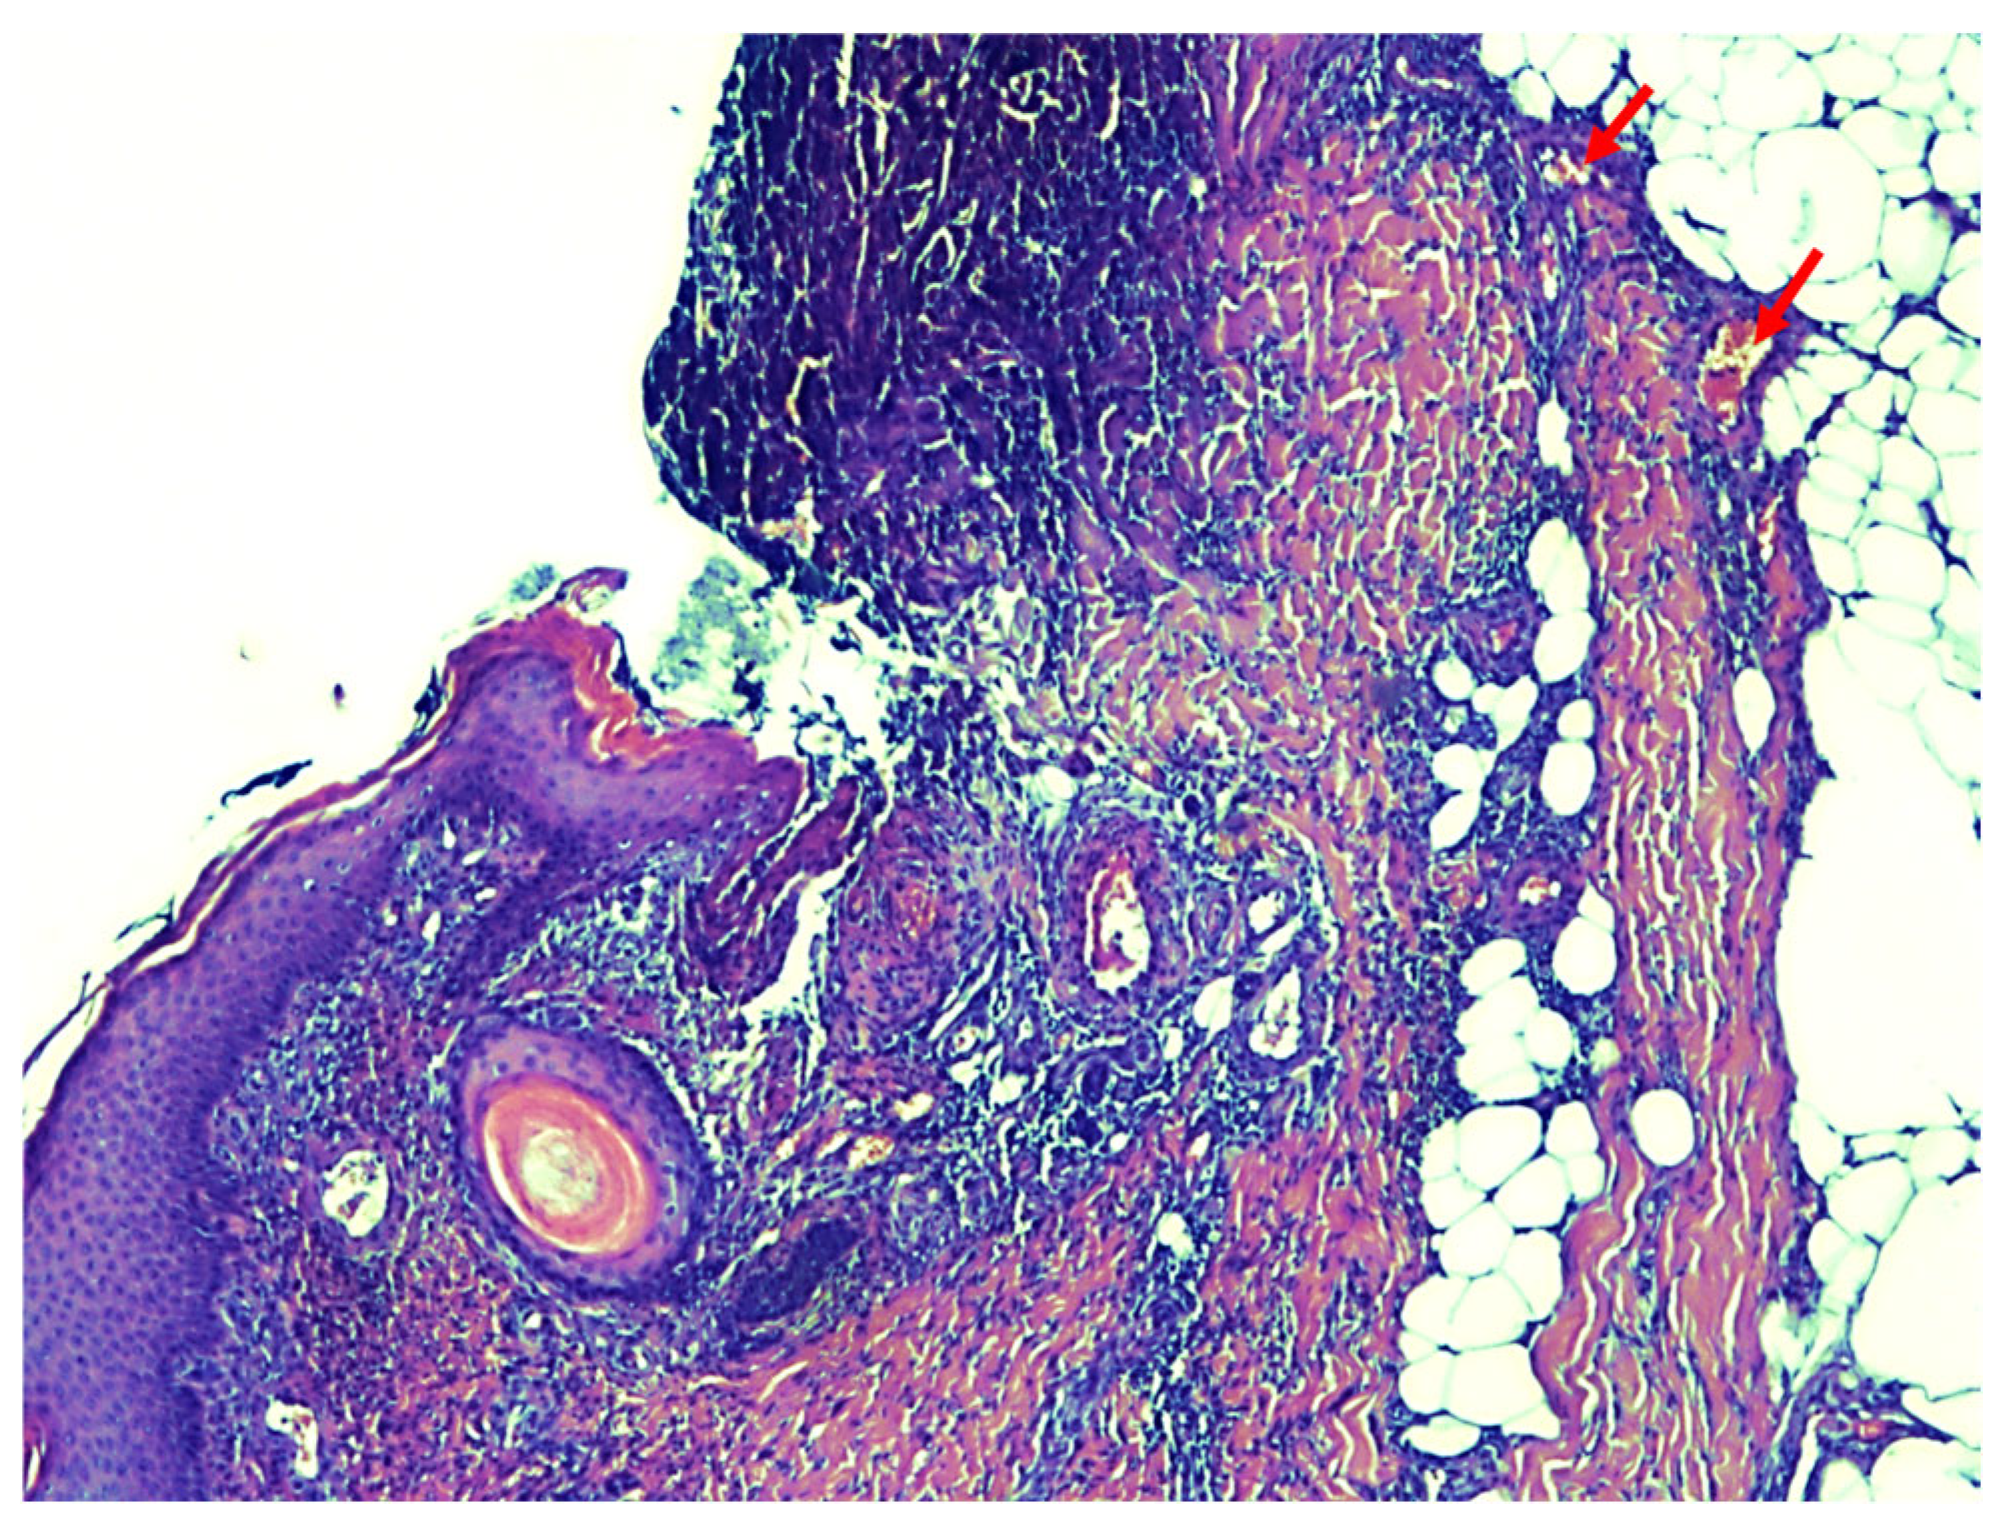

The histological examination results (Figure 4) described the presence of extensive superficial necrosis of the epidermis with complete destruction of the epithelium and spread of inflammatory infiltrate into the subcutaneous tissue in all samples. In various locations, mainly in the deeper dermis down to the subcutaneous adipose tissue, calcifications with proliferation of intimal fibroblasts were found in the walls of smaller vessels, and in some vessels, the occurrence of thrombosis was found. The patient was therefore diagnosed with calciphylaxis (July 2024). The postoperative period was complicated by partial lysis of the DE grafts, after which the patient underwent 15 sessions of hyperbaric oxygen therapy, lasting 120 min. This resulted in significant progress in the healing of the DE graft wounds. Hyperbaric oxygen therapy was delivered in a 13-seat Haux chamber. During each session, at a pressure of 1.6 bar, the patient inhaled 100% oxygen via a face mask. After discharge from the department, the patient was prescribed sodium thiosulfate. The patient continues to undergo wound dressing therapy, and the wounds are significantly smaller than the condition at the time of discharge.

Figure 4. The results of the histological examination show the presence of extensive necrosis of the epidermis and the presence of calcium deposits in the small deep dermal vessels (pointed to by red arrows).